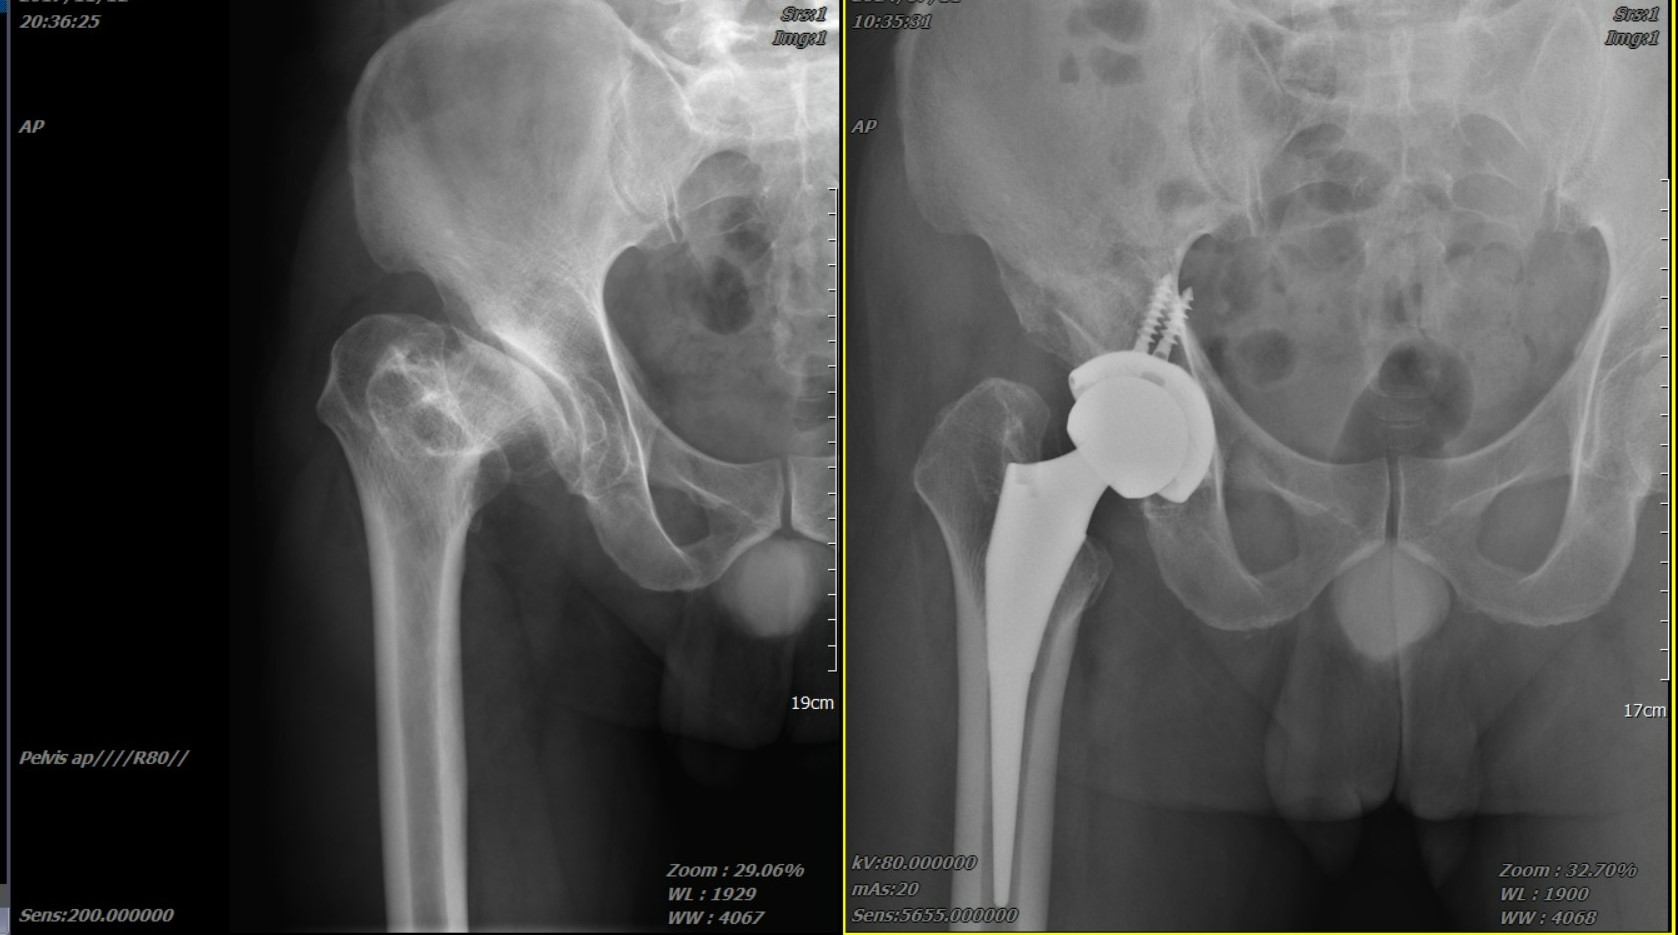

髖關節退化分期:您在哪個階段?

退化性髖關節炎在臨床上,我們常參考 Kellgren-Lawrence (K-L) 分級系統,這有助於患者理解為何醫師建議特定治療:

-

初期(第 1-2 級)

關節間隙輕微變窄,可能出現細小骨刺。患者常感到運動後局部痠痛,休息即可緩解。 -

中期(第 3 級)

間隙明顯狹窄,骨刺增生,軟骨磨損增加。此時 「牽涉痛」(如前述的膝蓋痛)會變得頻繁。 -

後期(第 4 級)

關節間隙幾乎消失,骨頭與骨頭直接磨擦,出現囊腫與硬化。此時生活品質嚴重受損,通常是微創髖關節手術的最佳介入時機。

理想的科技醫療方案:創新前外側微創髖關節置換手術

當保守治療(如物理治療、藥物)效果不佳時,手術介入就成為恢復生活品質的關鍵。張建鈞醫師團隊的核心優勢,在於結合 「創新微創手法」 與 「精準醫療科技」,為患者實現低疼痛、快復原的治療目標。

▋張建鈞醫師創新微創手法:前外側微創髖關節置換

這項手術的核心突破在於 「肌肉與關節囊的完整保留」。傳統手術需切斷多條肌肉才能進入關節,而張醫師獨創的「前外側微創入路」,是經由肌肉間的天然間隙進入,在不切斷任何肌肉與關節囊的前提下,完成精準的關節置換。

精準診斷是成功治療的關鍵

張建鈞醫師團隊強調,所有成功的醫療介入都奠基於 「精準診斷」。

影像學評估:透過 X 光檢查關節間隙,並進一步運用 核磁共振 (MRI) 或 電腦斷層 (CT) 判斷骨密度 (BMD) 與軟組織受損程度。